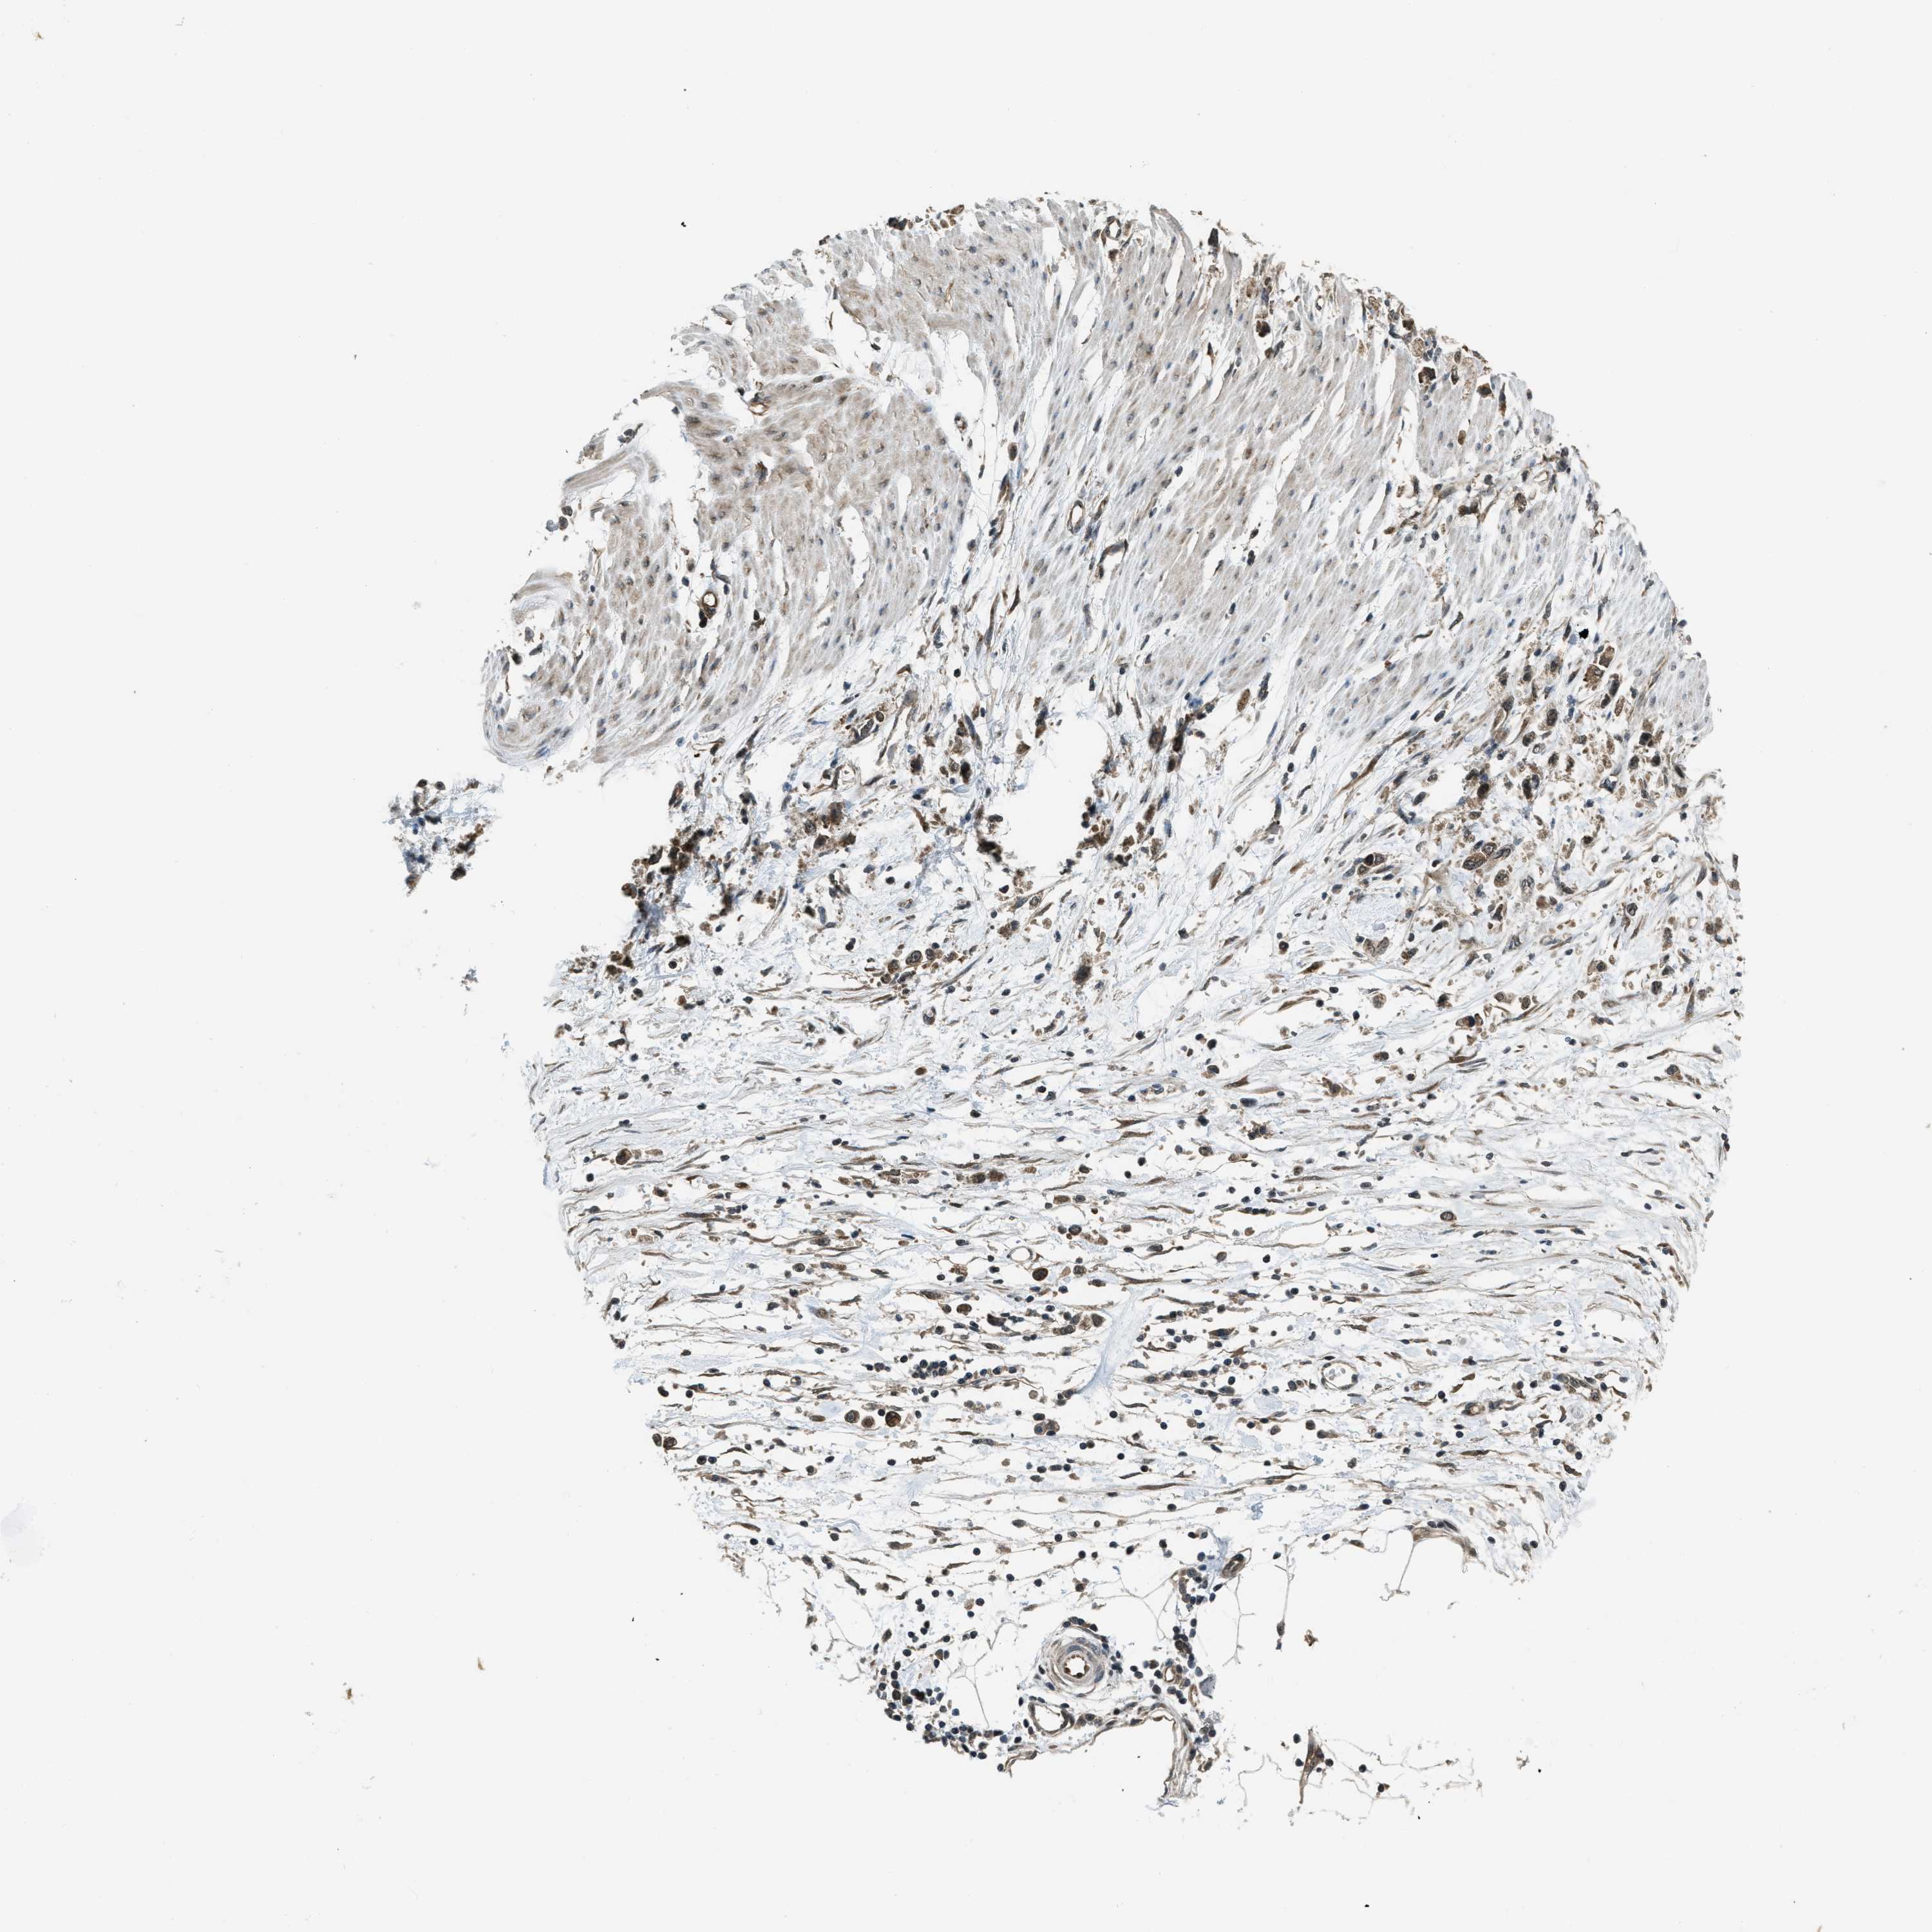

STOMACH CANCER - Protein expressioni

A mouse-over function shows sample information and annotation data. Click on an image to view it in a full screen mode. Samples can be filtered based on level of antibody staining by selecting one or several of the following categories: high, medium, low and not detected. The assay and annotation is described here.

Note that samples used for immunohistochemistry by the Human Protein Atlas do not correspond to samples in the TCGA dataset.

Antibody stainingi

Antibody staining in the annotated cell types in the current human tissue is reported as not detected, low, medium, or high, based on conventional immunohistochemistry profiling in selected tissues. This score is based on the combination of the staining intensity and fraction of stained cells.

Each image is clickable and will lead to virtual microscopy that enables deeper exploration of all samples and also displays staining intensity scores, fraction scores and subcellular localization as well as patient and tissue information for each sample.

Antibody CAB018615

Staining

High

Medium

Low

Not detected

Intensity

Strong

Moderate

Weak

Negative

Quantity

>75%

75%-25%

<25%

None

Location

Nuclear

Cytoplasmic/membranous

Cytoplasmic/membranous,nuclear

Adenocarcinoma, NOS

Adenocarcinoma, High grade